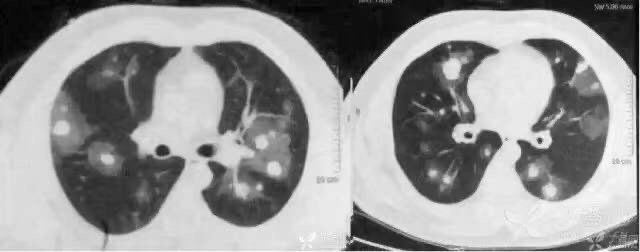

1. 1 病毒性肺炎:男性患者,29 岁,CT 示双肺弥漫性分布的片絮状、磨玻璃样影。

1.2 H1N1 肺炎:CT 显示双肺片絮状、磨玻璃样影呈弥漫性分布。